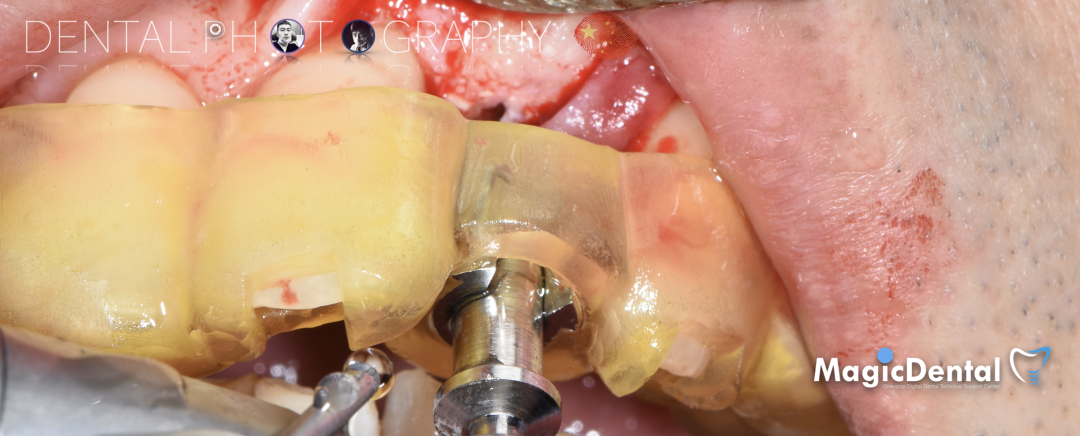

骨块细节

切开翻瓣,彻底暴露术区,试戴骨块。

调整骨块外形,适配受植区域,打开骨髓腔。

预备固位钉洞,固定骨块

骨膜减张,放置骨粉,放置骨块,钛钉固定骨块。

固定骨片,修整骨块边缘,继续放置骨粉覆盖骨块及受植区,放置骨膜,严密缝合创口。